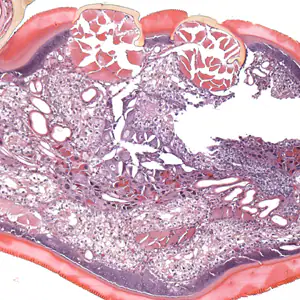

A skin biopsy specimen was collected from the clavicle region of a 45-year-old male who presented with what appeared to be a pigmented lesion. The patient resides in Kentucky and has no known international travel. The biopsy specimen was sent to Pathology for routine histologic work-up. Objects suggestive of an organism were examined on slides stained with hematoxylin-and-eosin (H&E). The attending pathologist captured images and sent them to CDC-DPDx for diagnostic assistance. Figures A–E represent five of the images received. What is your diagnosis? Based on what criteria?

Figure C